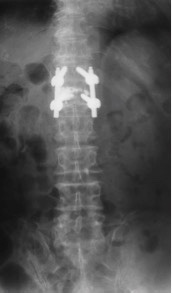

治疗:因患者椎体压缩骨折明显,椎体后缘骨折不完整,突入椎管,且硬膜囊受压,因此不适合行椎体成形术。给予单节段椎弓根钉固定并椎板切除减压术。骨折椎置钉结合钉道骨水泥加强稳定性。术后随访效果满意。

随访未见内固定松脱,无矫正丢失。